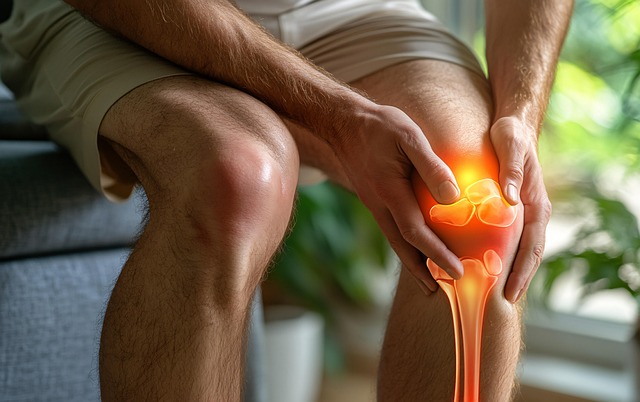

5. 무릎 통증 동반

고관절 문제는 무릎에도 영향을 미쳐 무릎에 통증을 유발할 수 있습니다. 이는 고관절과 무릎의 기능적 연관성 때문입니다.